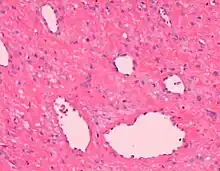

| Angiofibroma, Hematoxylin and eosin stain, magnification ×10. | |

AGF lesions share common macroscopic (i.e. gross) and microscopic appearances. Grossly, AGF lesions consist of multiple papules, one or more skin-colored to erythematous, dome-shaped nodules, or usually just a single tumor. Microscopically, they consist of spindle-shaped and stellate-shaped cells centered around dilated and thin-walled blood vessels in a background of coarse bundles of collagen (i.e. the main fibrous component of connective tissue).[2] Angiofibromas have been divided into different types but commonly a specific type was given multiple and very different names in different studies.[2]